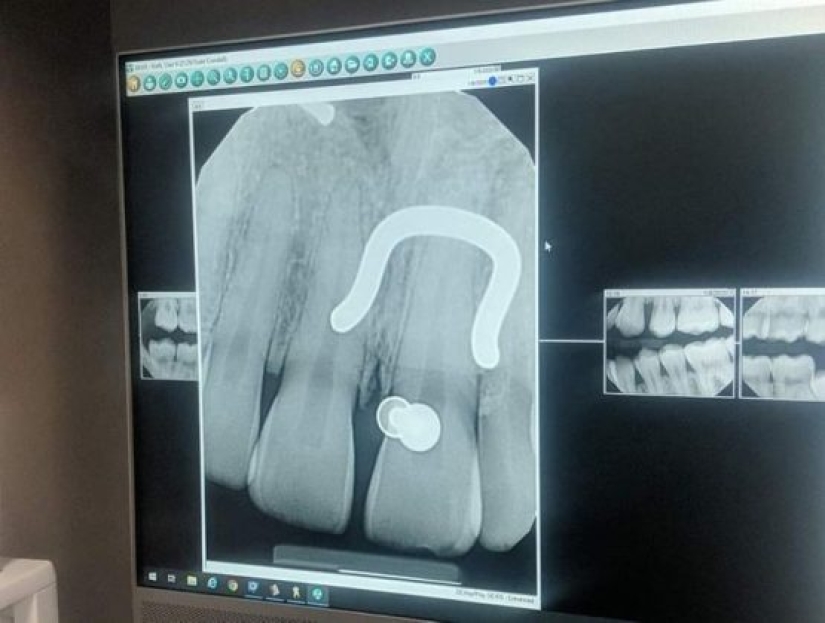

11. “At the moment the tooth fairy owes me a lot of money. I am 33 years old and here are my x-rays showing my remaining baby teeth.”